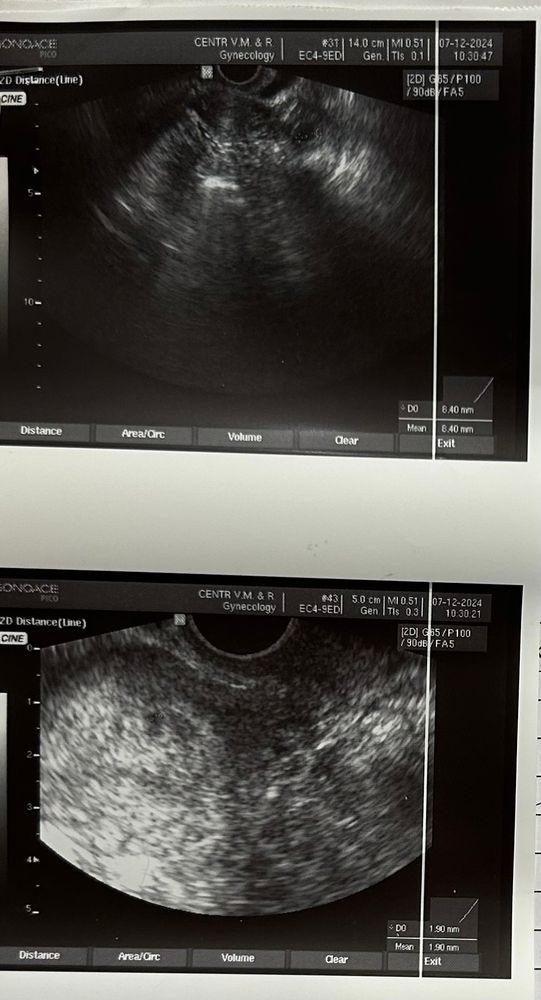

21 ДПО / 5(3) недели УЗИ

Сегодня 21 ДПО (3 эмбриональные недели). ХГЧ врач сказала больше не сдавать, дальше только следить по УЗИ за ростом ПЯ и за состоянием в целом.

ПЯ малютка 2 мм в матке (не маленькое ли?) + назначили в поддержку Дюфастон, потому что ЖТ всего 8 мм (хотя уровень прогика входит в норму), решили перебдеть, мало ли до следующего УЗИ деградирует.